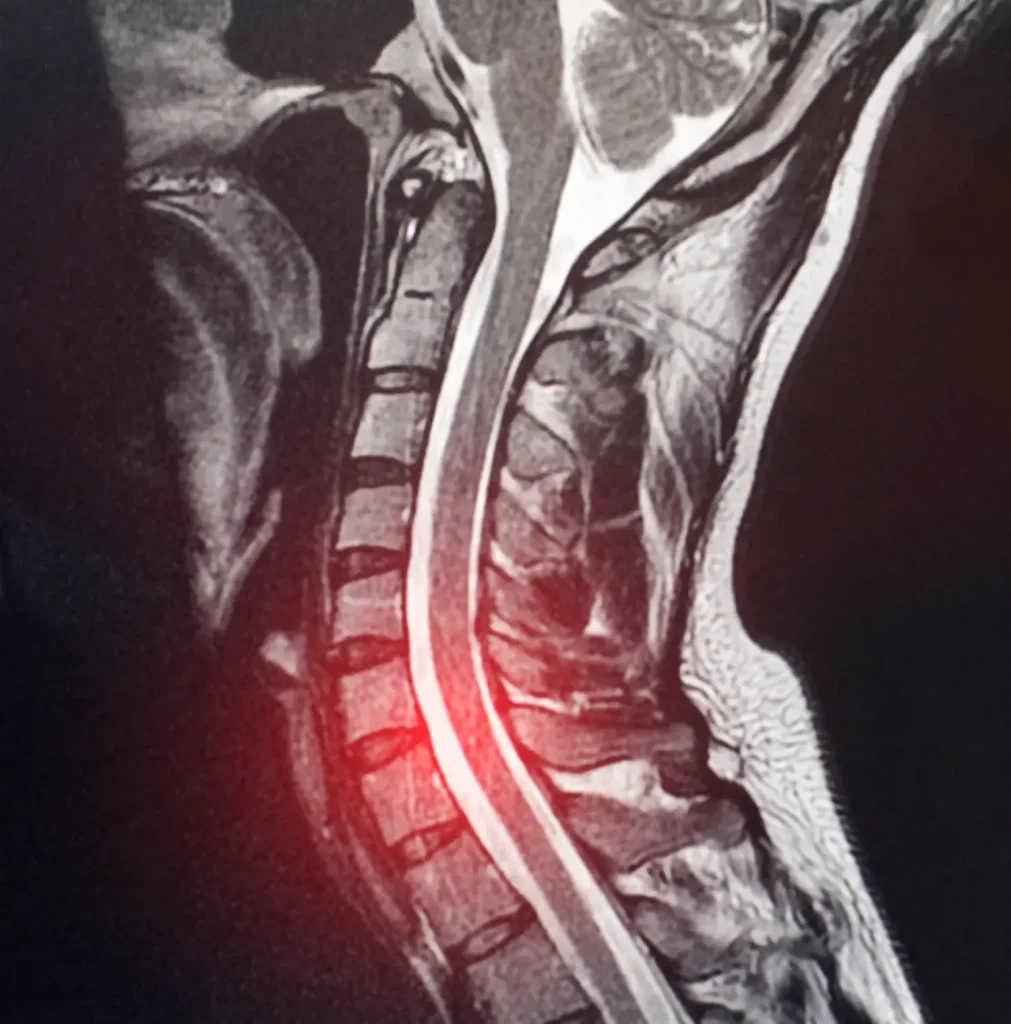

Magnetic Resonance Imaging (MRI): The gold standard for diagnosing cervical disc herniation. MRI provides detailed visualization of soft tissues, including the intervertebral discs, spinal cord, and nerve roots. It can reveal:

- The location and size of the disc herniation

- The degree of neural compression

- Spinal cord changes (if present)

- Other degenerative findings

A 2024 study emphasized that MRI is essential even when X-rays and CT scans appear normal, particularly when neurological symptoms are present (6). Don’t hesitate to request an MRI if your symptoms suggest nerve compression, but initial imaging was negative.